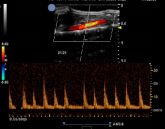

小鼠-腹主动脉彩色血流 小鼠-腹主动脉频谱多普勒 小鼠-左心室短轴 小鼠-心脏彩色血流